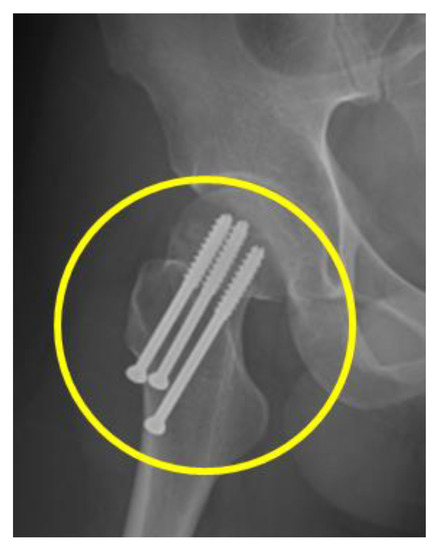

2. Case Presentation